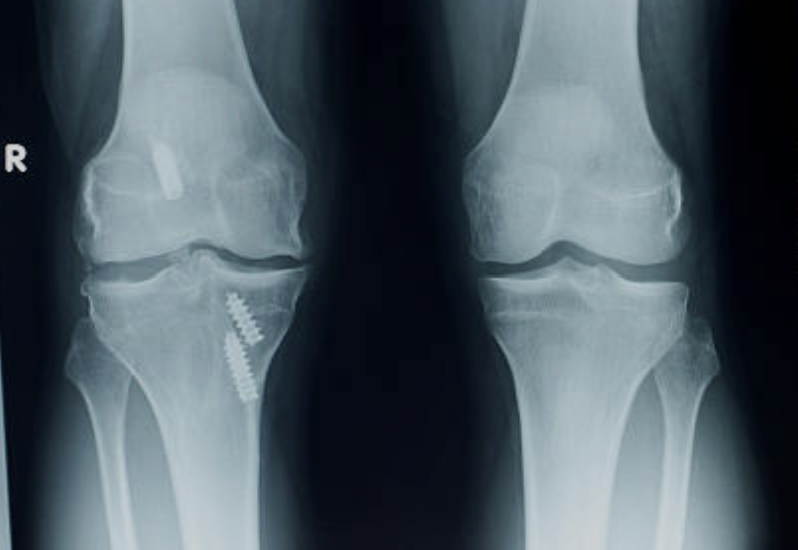

- 봉합술: 파열된 범위를 꿰메 주는 수술입니다. 파열의 형태에 따라 전방십자인대 견열 골절이거나 인대 부착 부 파열의 경우 봉합술을 할 수 있습니다.

- 재건술: 새로운 인대로 만들어 주는 수술입니다. 자신의 힘줄을 사용하거나 다른 사람의 힘줄을 사용하는 방식으로 진행됩니다. 관절내시경과 최소 침습 기법을 사용하여 수술 부위의 손상과 회복 기간을 줄일 수 있습니다.